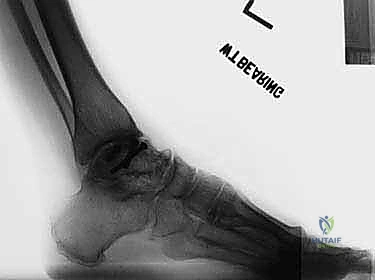

تبدأ رحلة العلاج مع الأستاذ الدكتور محمد هطيف بتقييم شامل. يتم إجراء فحوصات دموية كاملة، وتخطيط للقلب، والأهم من ذلك: التصوير الطبي المتقدم.

يعتمد الدكتور هطيف على الأشعة السينية (X-rays) والأشعة المقطعية (CT Scans) ثلاثية الأبعاد لبناء خريطة دقيقة للتشوهات العظمية وتحديد حجم ومسار المسمار النخاعي المناسب لكل مريض بدقة متناهية. يتم مناقشة كل هذه التفاصيل بشفافية تامة مع المريض.